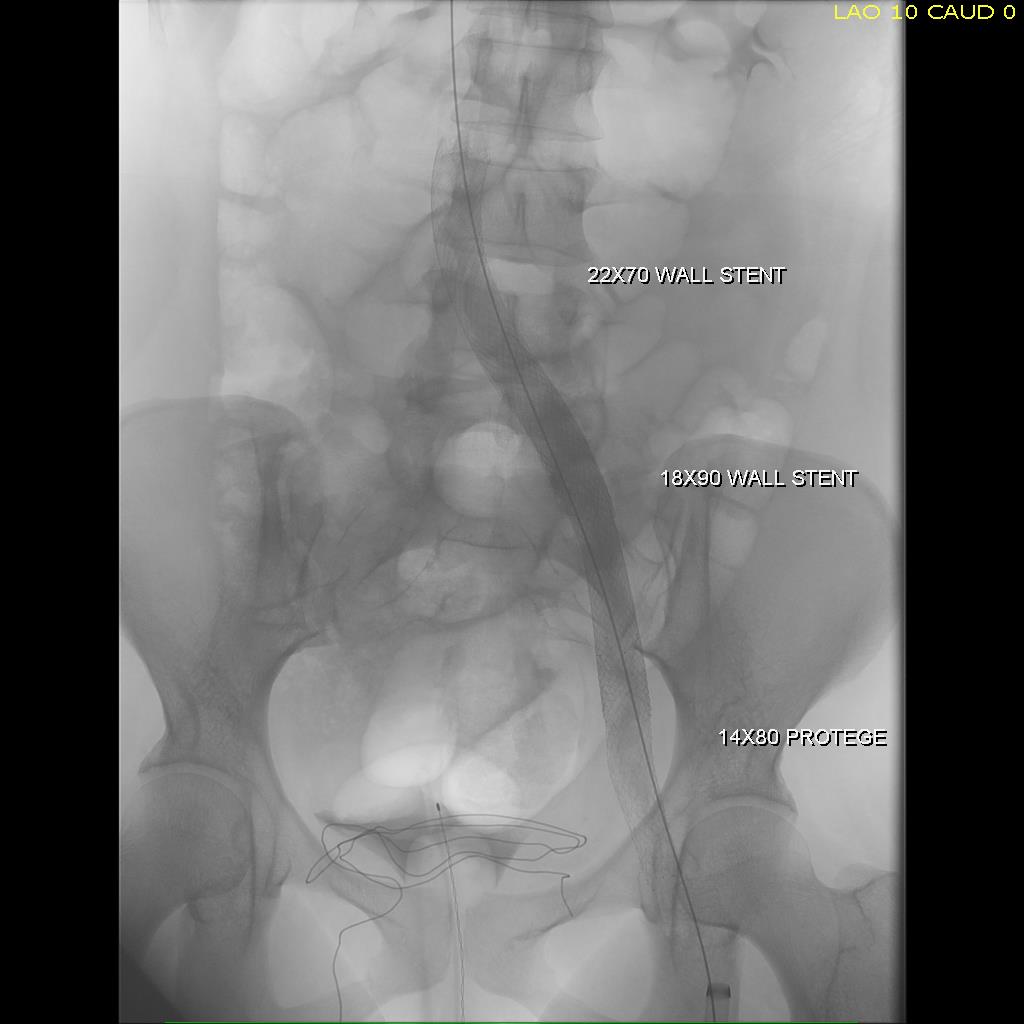

Once this is done, the iliac veins are dilated to 14mm from the IVC to the common femoral arteries. large 18mm Wall stents are deployed in a kissing fashion from the caval stent into both iliac systems and dilated to 18mm.

intervention fig 6.png

Predilatation of iliac venous systems with ever larger balloons, deployement of bilateral 18mm Wall Stents

After deployment, the Wall Stents are ballooned to 18mm. These stents were extended into the common femoral artery with 14mm nitinol stents.

intervention fig 7.png

Ballooning 18 mm Wall Stents with 18mm Atlas balloons, then extending to CFA with nitinol stents of 14mm

Completion venography suggested successful iliocaval recanalization and revascularization but these procedures are not done without a final intravascular ultrasound (IVUS).

Looks done, but needed final intervention after IVUS.

Intravascular ultrasound revealed incomplete expansion of the right common femoral stent. This was treated with another stent and ballooning with the result on the right.

Stent compression on IVUS treated with second stent

Venography alone is insufficient in determining patency. As illustrated, IVUS ensures a durable outcome.